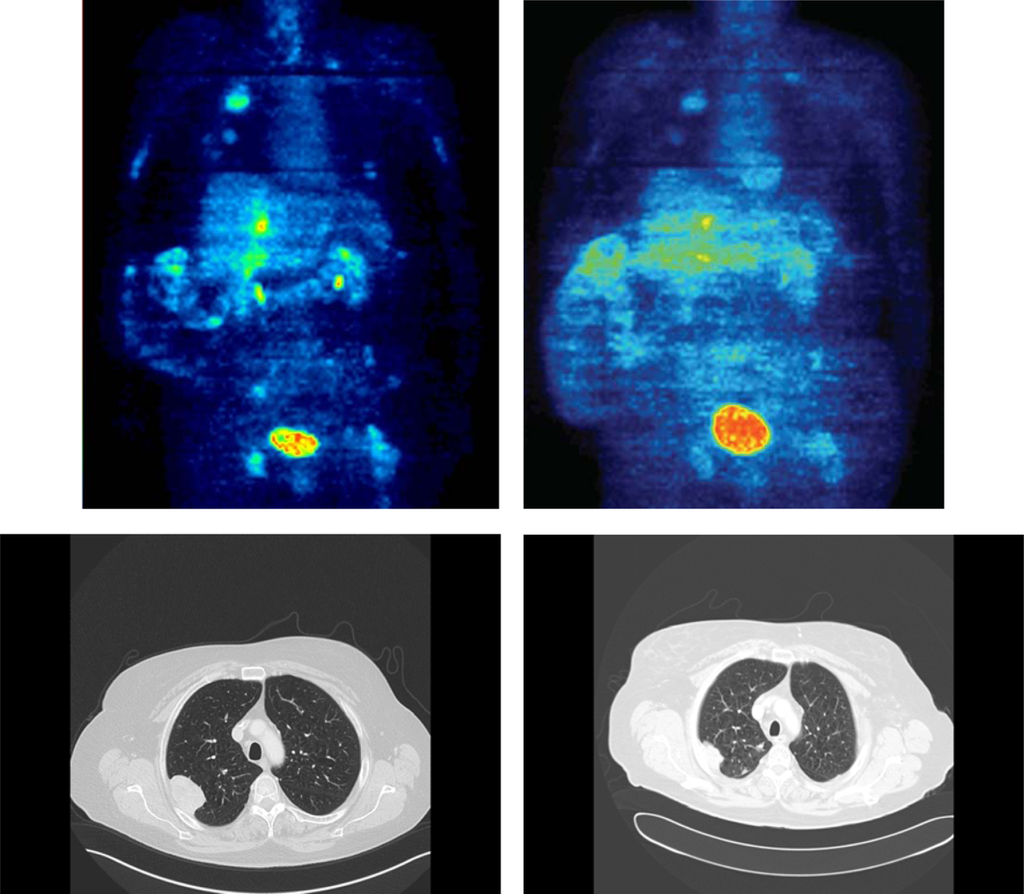

Example

In order to demonstrate that PET imaging may provide additional information compared to conventional MRI and/or CT, we describe a case from one of our patients (Figure 1): A 62 year old female with a leiomyosarcoma, grade III, of the vena cava with lung and liver metastases. The FDG PET prior therapy with trabectedin showed an average SUV of 6.7 and a SUVmax of 13.5 (upper left image). After three cycles of treatment with trabectedin, the FDG PET demonstrated a decrease of the average SUV to 3.5 and of the SUVmax to 6.1 (upper right image) and a decrease of the FDG uptake in all other evaluable lesions. The corresponding conventional CT documented PR according to RECIST (lower left and right images). This case underlines the common finding that the structure of the tumour may change reflected by a decline of the average and the maximum SUV caused by a change of the vessel density, blood circulation or necrosis even though the tumour size itself remains rather stable.

Figure 1. Case of a 62 year old female with a leiomyosarcoma, grade III, of the vena cava with lung and liver metastases. FDG PET showed a decrease of the average SUV from 6.7 and of the SUVmax from 13.5 (upper left image) to 3.5 and 6.1 (upper right image), respectively, as well as a decline of the FDG uptake in all evaluable lesions (mSUV PET images, colour-scales are directly comparable (0–10 SUV)). As an example, the corresponding CT scan showed the reduction in size of one reference lesion in the lung demonstrating a PR according to RECIST criteria (lower left and right images). Additionally, liver metastases demonstrated a partial remission (not shown).